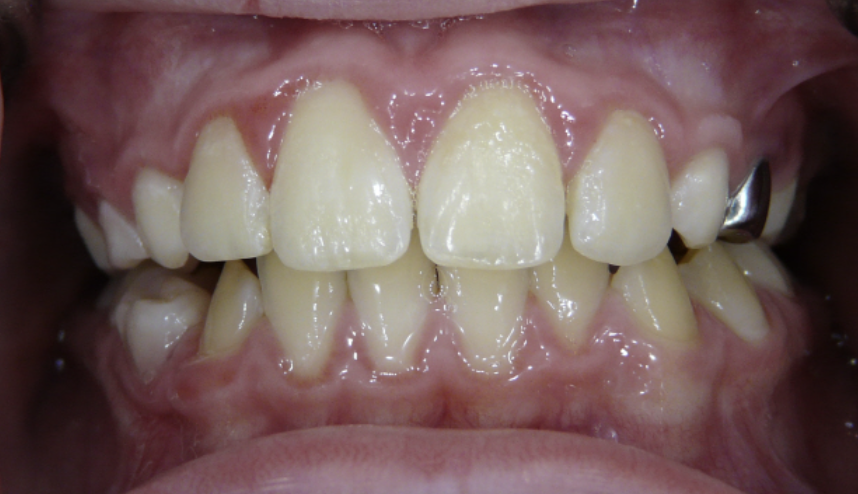

Anterior Crossbite

Top teeth are behind bottom teeth.